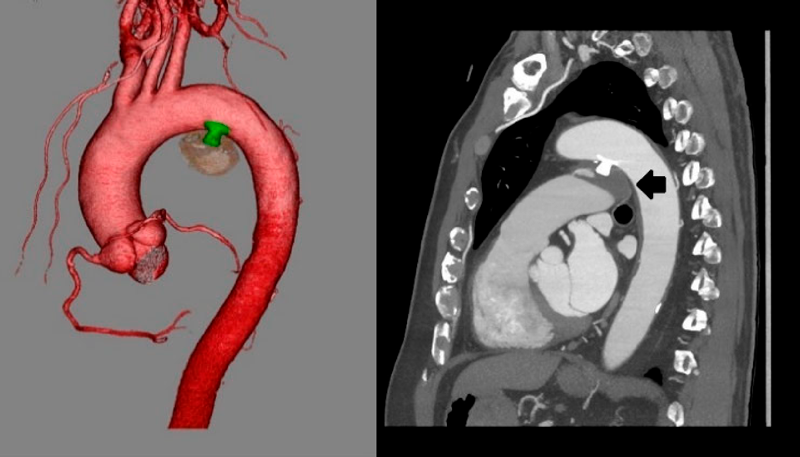

入院翌日に経皮的動脈管閉鎖術を施行した.局所麻酔後,右大腿静脈に6 Fr 11 cm sheath(Medikit Inc., Tokyo),右大腿動脈に5 Fr 11 cm sheath(Medikit Inc., Tokyo)を留置した.カテーテル検査の結果Qp/Qsは1.05,肺血管抵抗係数は0.57 Wood unit·m2.大動脈造影でDAAが造影され,瘤入口部径は5.4 mm,瘤最大径は28.9×37.2 mm,瘤流出部径は2.2 mmであった(Fig. 3a).5 Frジャドキンス型右冠動脈用(JR)カテーテル(Hanaco Medical, Saitama, Japan)を逆行性に進めて瘤入口部にかけて,そこから0.035̋Radifocus guidewire 260 cm(Terumo Inc., Tokyo)を瘤内へ進めて,1ループさせて主肺動脈まで進めた.続いて,順行性に進めて主肺動脈に留置した6 Fr wedge pressure catheter(Gadelius Medical, Kanagawa, Japan)から15 mm径の6 Fr Amplatz goose neck snare (Medtronic plc., Ireland)を進めて,Radifocus guidewire先端を把持して(Fig. 3b)右大腿静脈のsheath外まで引き出した.瘤内のループを伸ばして,大腿静脈–DAA–大腿動脈のwire loopを作成した(Fig. 3c).DAAの大動脈側入口部径が5.4 mmであったため,ADO 12 mm/10 mm(Abbott Structural Heart, Plymouth, MN, USA)を同部に留置した:右大腿静脈のsheathを抜去し,7 Fr Amplatzer™ TorqVue 180 (Abott, Pylmouth, MN, USA)を下行大動脈まで進めた.ADOのRetention skirtを展開して瘤入口部にかけて,デバイスボディを瘤内に展開した.留置後の大動脈造影では閉鎖栓突出による大動脈の狭窄はなく,遺残短絡はごく少量であった(Fig. 3d).特に合併症は認めず,治療翌日からアスピリン100 mgの内服を開始し,退院した.治療後の経過は良好で,術後1カ月の心臓超音波検査で遺残短絡は消失し,術後3カ月の胸部造影CT像で瘤内はほぼ血栓化していた(Fig. 4).

Pediatric Cardiology and Cardiac Surgery 41(2): 84-88 (2025)

Fig. 3 Percutaneous closure of a DAA

a: DAA size: Ao side, 5.6 mm; PA side, 2.2 mm; and maximum diameter, 37.2×28.9 mm. b: The distal end of the Radifocus guidewire is snared in the MPA. c: The Radifocus guidewire is withdrawn into the 6 Fr right femoral sheath to form a wire loop. d: After device deployment, aortic angiography shows no residual leakage from the DAA. DAA, ductus arteriosus aneurysm; MPA, main pulmonary artery.

Fig. 4 Contrast-enhanced chest computed tomography revealing that the DAA is almost thrombosed (black arrow)

DAA, ductus arteriosus aneurysm.